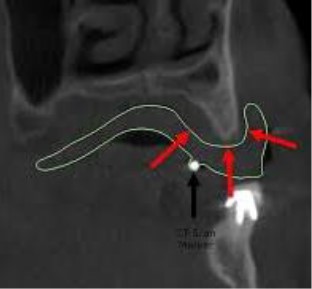

Dry denture and place 3-4

markers on the Buccal flange

on different planes and 3-4

markers on the lingual or

palatal for a total of

6-8 markers